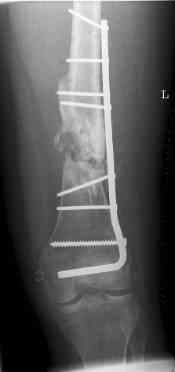

16 yr old boy, high energy motorcycle trauma trauma in July 2005 with:

- distal femoral fracture L

july 05: LISS femur, LCP plate tibia, double recon. plate post. acetabulum

aug 06: blade plate + bone graft

nov 06: revision blade plate

feb 07: retrograde nail + bone graft + BMP

nov 07: persistant non-union distal femur; other fractures healed